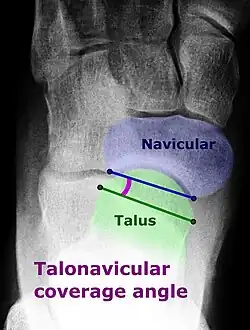

On plain radiography, flat feet can be diagnosed and graded by several measures, the most important in adults being the talonavicular coverage angle, the calcaneal pitch, and the talar-1st metatarsal angle (Meary's angle).[11] The talonavicular coverage angle is abnormally laterally rotated in flat feet.[11] It is normally up to 7 degrees laterally rotated, so a greater rotation indicates flat feet.[11] Radiographies generally need to be taken on weightbearing feet in order to detect misalignment.[12]

Dorsoplantar projectional radiograph of the foot showing the measurement of the talonavicular coverage angle.

Dorsoplantar projectional radiograph of the foot showing the measurement of the talonavicular coverage angle. -